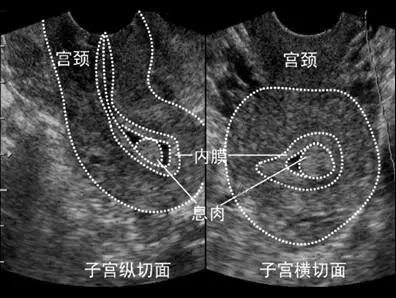

首先,進入試管嬰兒(IVF)周期治療前需行一次全面的超聲檢查。目的是初步測量子宮和卵巢的大小、篩查子宮畸形、附件或盆腔內病變和包塊,評估雙側卵巢儲備狀況。必要時還需三維超聲檢查,進一步明確子宮及宮腔形態,以排除IVF治療的禁忌癥;

1)基礎狀態的超聲監測:月經第1~5天進行,目的是評估盆腔的基礎狀態,包括卵巢、內膜評估和盆腔是否存在異常情況,為內膜準備方案提供依據。

3)激素替代周期:根據藥物的使用時間進行超聲監測,關注點主要是內膜的厚度及分型,直至確定您的移植日期。